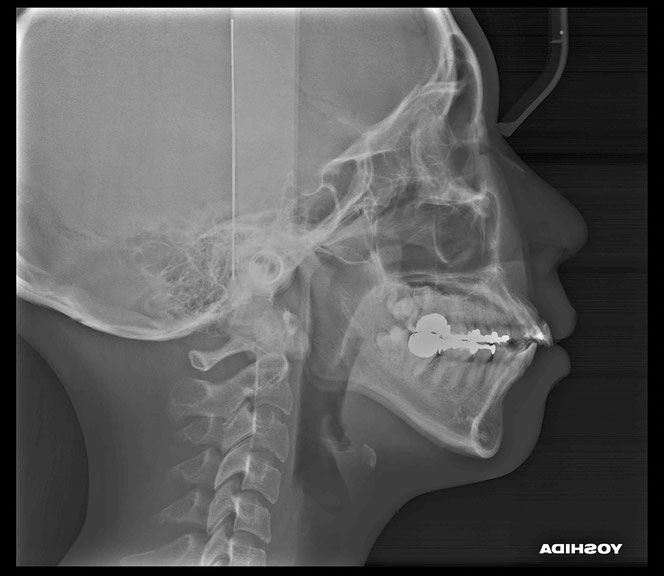

こんな方は要注意

✔ 矯正後に歯ぐきが下がった

✔ 歯の根元が黒っぽくなってきた

✔ 奥歯の根元がしみる

✔ 歯が長くなった気がする

放置すると、知らない間に虫歯が進行することもあります。